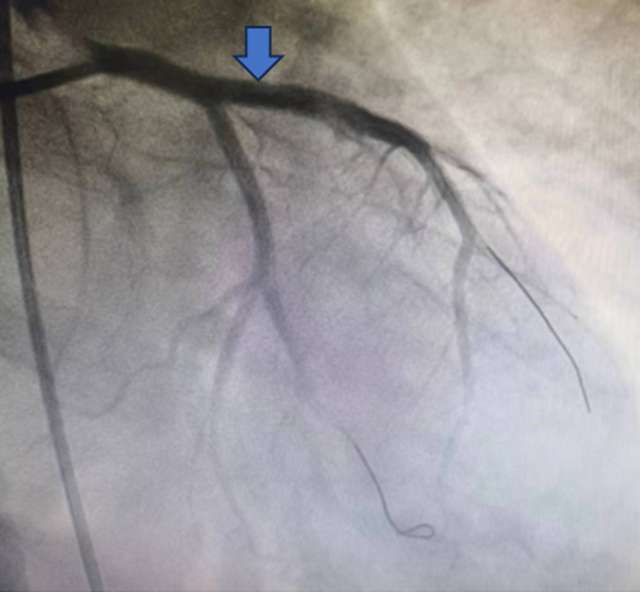

2月26日上午12:50分,李大爷被送入导管室,由于李大爷大面积心肌梗死导致血压低,并且处于昏迷状态,魏刚当机立断,指导当地心内科医生直接穿刺股动脉而不是常规的桡动脉,为李大爷进行了冠状动脉造影、冠状动脉支架植入手术。凭借丰富的经验,手术用时不到20分钟,穿刺、造影、支架植入一气呵成,顺利帮助李大爷闯过了冠状动脉梗阻“关”。

(患者冠脉支架植入前、后对比图)